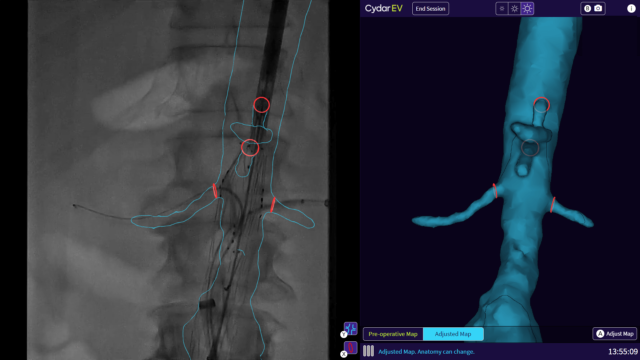

Cydar Maps is the first product from Cydar’s AI technology platform and, according to the company, transforms the way information is provided to clinicians undertaking image-guided minimally invasive surgery (MIS) simplifying complexities within operating theaters at leading hospitals across the globe.

The company explains that Cydar Maps generates a 3D map of patient soft tissue to support and integrate preoperative planning, intraoperative guidance and postoperative review of endovascular MIS, using AI to update the map throughout the patient journey. Cydar Maps has been shown to offer a number of benefits, a company press release reports, including halving the radiation exposure for patients and the clinical team, simplifying the clinical workflow and increasing clinician confidence, which in turn can significantly reduce procedure times.